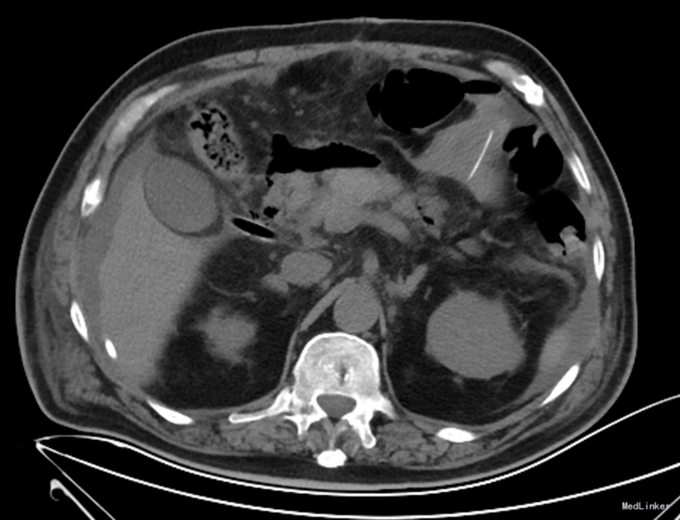

查体:体温36.5℃,呼吸:18次/分,心率89次/分,血压115/79mmHg。神清语明,步入病房,查体合作。贫血貌,周身皮肤及粘膜无黄染及出血点,浅表淋巴结未触及肿大,颈静脉无充盈。巩膜无黄染,睑结膜苍白,口唇无发绀。双肺听诊呼吸音清,双肺未闻及明显干湿罗音。心音低钝,律齐,听诊心率66次/分,各瓣膜听诊区未闻及病理性杂音。腹部无压痛,无反跳痛及肌紧张,肝脾肋下未触及,无肝肾区叩击痛。双下肢无水肿。 辅助检查:腹部增强CT:胃窦部小弯侧溃疡病变,恶性可能性大。

诊断:胃癌;中度贫血;冠心病陈旧性心肌梗死;高血压2级(极高危);冠脉造影及支架植入术后 治疗:全麻下行胃癌根治切除(D2)、Billorth-I式吻合、空肠营养造瘘术,手术顺利,术后恢复可,术后第7天,患者突然出现右侧腹部疼痛,后转移至下腹及左侧髂腹部等,吻合口后引流管引流出暗黄色浑浊液体,留置胃管后引流出同性质液体,考虑吻合口瘘,复查全腹CT平扫,肝周积液较前增多。请介入科行肝周积液的穿刺引流,同时经空肠营养管予肠内营养,但患者仍持续高热,经介入科第二次穿刺引流后,患者体温由39.5℃逐渐下降至正常。